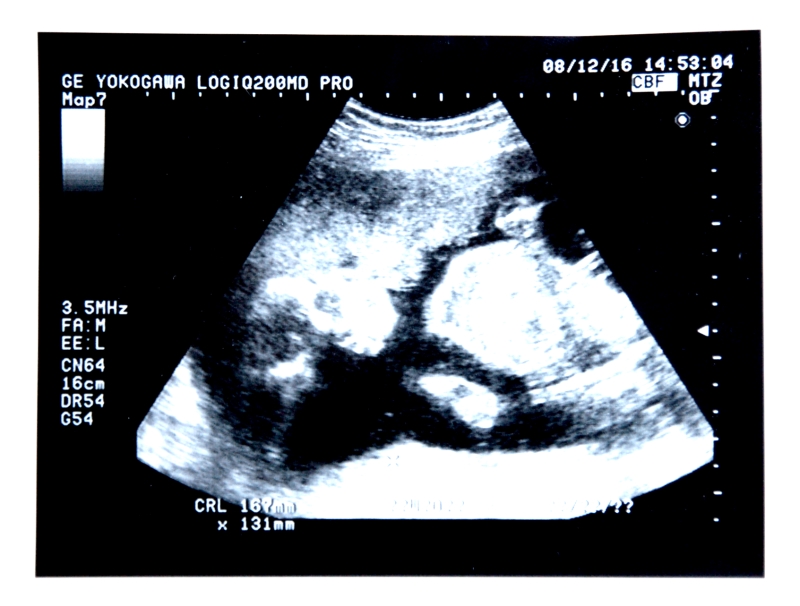

妊娠7か月(24、25、26、27週)の赤ちゃんの状態

身長は35cm程度、体重は700~1000グラム。

顔立ちがしっかりしてきて、目を開けたり閉じたりできるようになります。超音波検診では、あくびや指しゃぶりの様子が見られることもあります。目撃すると、かなり感動しますヨ。